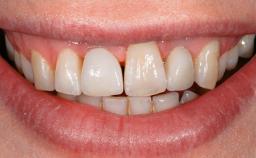

This case describes the ongoing management of a 64-year-old healthy, non-smoking female patient with erosive oral lichen planus (OLP) affecting the gingivae and the buccal and lingual mucosa. The peri-implant mucosa was also affected subsequent to implant placement. The patient had osseointegrated implants (four in the maxilla, four in the mandible) placed following extraction of hopeless teeth and a healing period. The patient had a history of OLP prior to implant placement and had been referred to an oral-medicine specialist for definitive diagnosis and treatment. She exhibited generalized oral mucosal involvement. Following a clinical assessment, biopsy, and blood tests, she was treated with topical corticosteroids. Systemic prednisolone was reserved for severe flare-ups. Amphotericin lozenges were used in combination with corticosteroid treatment to prevent the development of oral candidiasis.

Lip Line No exposure of papillae Exposure of papillae Full exposure of mucosa margin

Periodontal Phenotype Low-scalloped, thick Medium-scalloped, medium-thick High-scalloped, thin